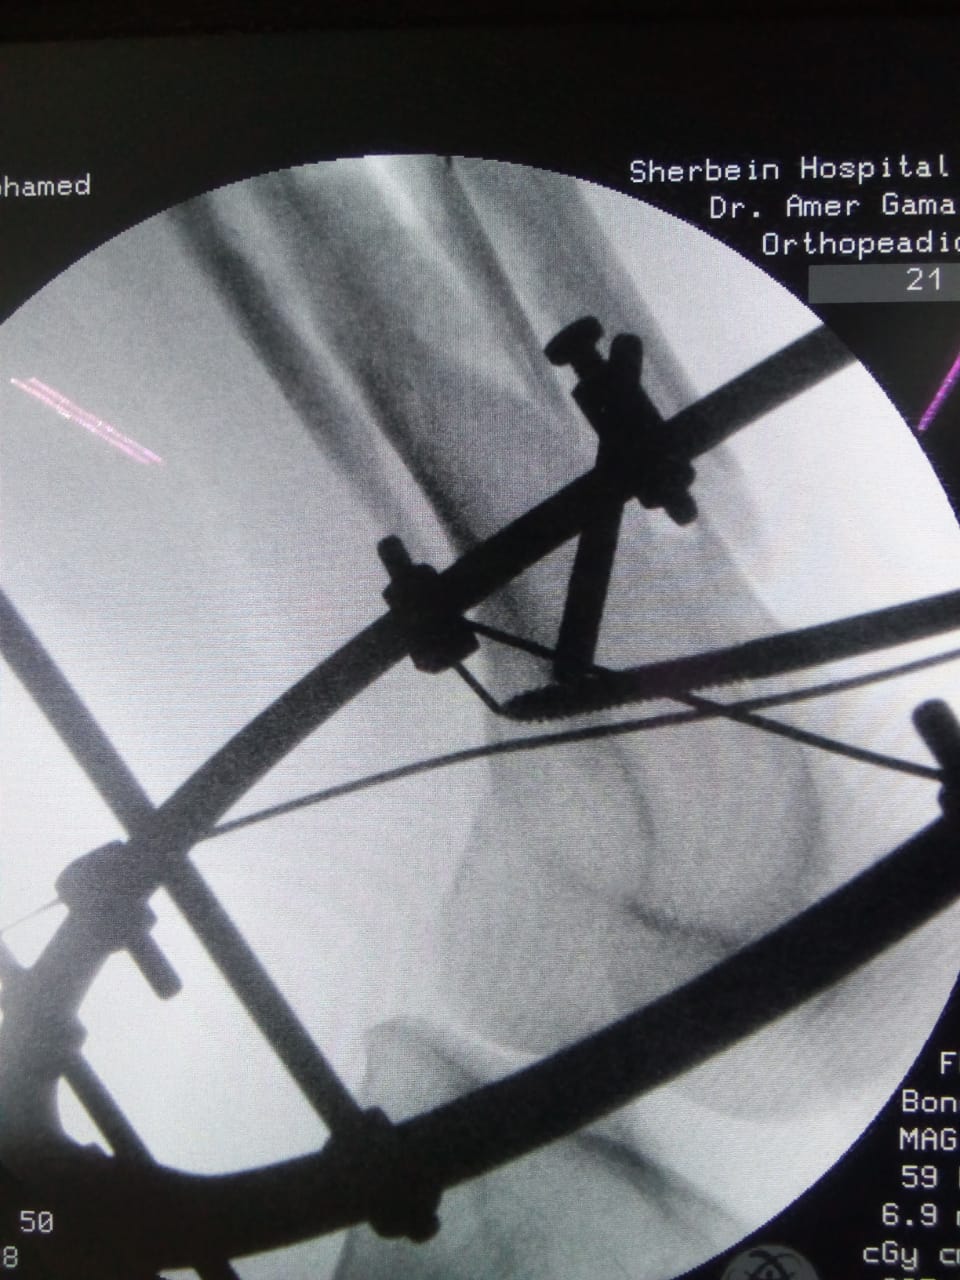

أعلن الدكتور سعد مكي، وكيل وزارة الصحة بالدقهلية، مساء اليوم، نجاح فريق طبي في إجراء تدخل جراحي دقيق لشاب يعاني من كسر مضاعف من الدرجة الثالثة إثر طلق ناري أدى إلى تهتك بالأنسجة وكسور متفتتة بالفخذ.

وتمكن الفريق الطبي من إجراء الجراحة عن طريق جهاز الليزاروف في واحدة من عمليات العظام الكبرى بمستشفى شربين المركزي، وهي تعد من العمليات المتقدمة ذات المهارة الخاصة.